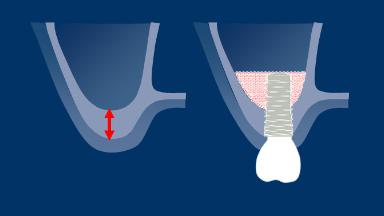

Um histórico completo e exame clínico são essenciais ao planejar a substituição de dentes por implantes dentários. Antes da cirurgia, as avaliações clínicas e radiográficas específicas do local devem ser cuidadosamente conduzidas. Essas avaliações fornecerão as informações necessárias para formular um plano de tratamento detalhado e individualizado, capaz de atender às expectativas realistas do paciente. Portanto, um exame abrangente é obrigatório para antecipar quaisquer complicações que possam resultar do tratamento. Neste módulo, discutiremos os exames específicos da região recomendados e sua relevância para pacientes que consideram substituir um ou mais dentes por implantes dentários. As avaliações específicas da região que serão discutidas neste módulo são o espaço restaurador e suas características, fatores anatômicos e tecidos duros e moles, incluindo quaisquer patologias na área.

- avaliar o espaço protético e suas características

- avaliar os tecidos moles e duros